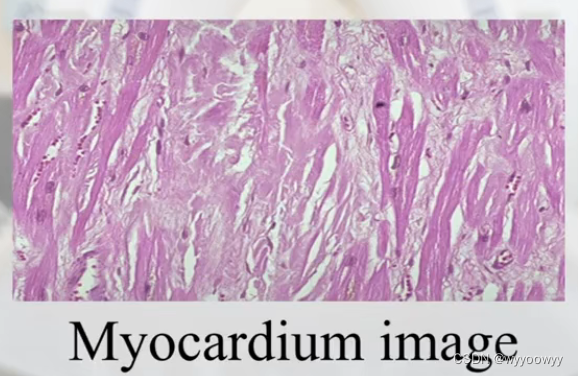

8、医学图像的类别

彩色图像:三个灰度图像的叠加 RGB,三个channel

显微图片